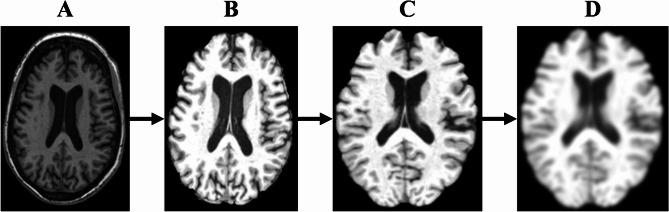

Alzheimer's disease (AD) constitutes a neurodegenerative disorder predominantly observed in the geriatric population. If AD can be diagnosed early, both in terms of prevention and treatment, it is very beneficial to patients. Therefore, our team proposed a novel deep learning model named 3D-CNN-VSwinFormer. The model consists of two components: the first part is a 3D CNN equipped with a 3D Convolutional Block Attention Module (3D CBAM) module, and the second part involves a fine-tuned Video Swin Transformer. Our investigation extracts features from subject-level 3D Magnetic resonance imaging (MRI) data, retaining only a single 3D MRI image per participant. This method circumvents data leakage and addresses the issue of 2D slices failing to capture global spatial information. We utilized the ADNI dataset to validate our proposed model. In differentiating between AD patients and cognitively normal (CN) individuals, we achieved accuracy and AUC values of 92.92% and 0.9660, respectively. Compared to other studies on AD and CN recognition, our model yielded superior results, enhancing the efficiency of AD diagnosis.

阿尔茨海默病(AD)是一种主要在老年人群中观察到的神经退行性疾病。如果能在预防和治疗方面早期诊断出AD,对患者非常有益。因此,我们的团队提出了一种名为3D-CNN-VSwinFormer的新型深度学习模型。该模型由两个部分组成:第一部分是配备了3D卷积块注意力模块(3D CBAM)的3D卷积神经网络,第二部分是经过微调的视频Swin Transformer。我们的研究从个体层面的3D磁共振成像(MRI)数据中提取特征,每个参与者仅保留一张3D MRI图像。这种方法避免了数据泄露,并解决了二维切片无法捕捉全局空间信息的问题。我们利用阿尔茨海默病神经影像倡议(ADNI)数据集来验证我们提出的模型。在区分AD患者和认知正常(CN)个体时,我们分别获得了92.92%的准确率和0.9660的曲线下面积(AUC)值。与其他关于AD和CN识别的研究相比,我们的模型产生了更优的结果,提高了AD诊断的效率。